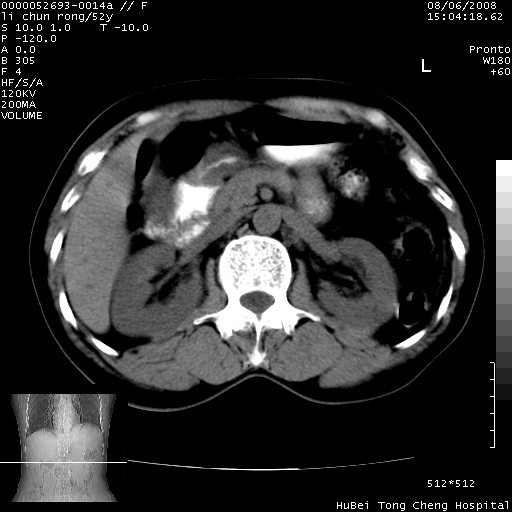

以下是引用云翔在2008-8-7 6:20:00的发言:[br]胰尾部囊性病变,考虑假囊肿,结合实验室检查疾病史

以下是引用zjzjr在2008-8-7 8:38:00的发言:[br]支持胰腺炎伴假囊肿形成,左肾小囊肿.少量腹水.

以下是引用随光逐影在2008-8-7 9:12:00的发言:[br]1)考虑胰腺炎伴假性囊肿形成可能性大;胰腺囊腺瘤待排。2)左肾小囊肿。3)少量腹水。